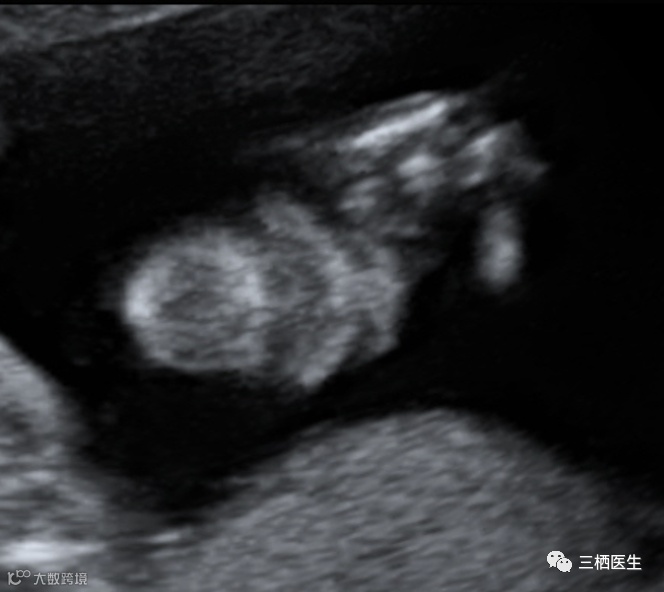

病例:孕妇32y,G2P1,孕20+周,无特殊家族史,常规排畸超声如下发现:

上唇线及牙槽骨连续

超声诊断:继发腭裂(软腭及硬腭裂)。